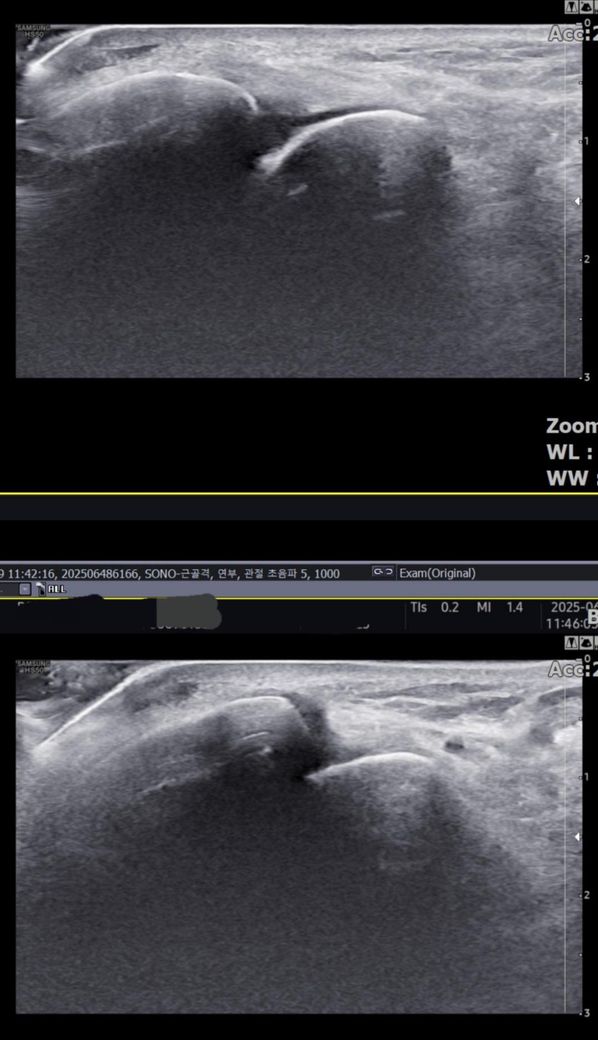

그런데 다친 지 2주 뒤부터 발목이 쑤시듯 아파 병원에서 초음파 검사를 했고, 전거비인대(ATFL) 2도 염좌 진단을 받았습니다. 이후 약 6주 동안 주 1회씩 충격파, 물리치료, 도수치료 등을 받았습니다. (고정치료는 시기가 늦었다며 진행하지 않았습니다.)

그리고, 처음 초음파 사진(6월 촬영)과 비교하여

mri 사진(8월 촬영)상 인대가 호전됬는지도

알고 싶습니다.

올려주신 mri를 보면 전거비인대는 연속성이 유지되고 있고 파열이나 큰 손상 흔적은 없어 재활로 회복 가능한 상태로 보입니다 다만 3개월 가까이 활동 시 통증과 미열감이 남아 있는 것은 조직 회복이 아직 완전히 끝나지 않았거나 주변 연부조직 관절 움직임 제한 등으로 인한 과민 반응일 수 있습니다.

초음파와 비교하면 mri 상으로 인대 연속성이 확인되므로 심각한 악화나 재파열은 아닌 것으로 판단됩니다